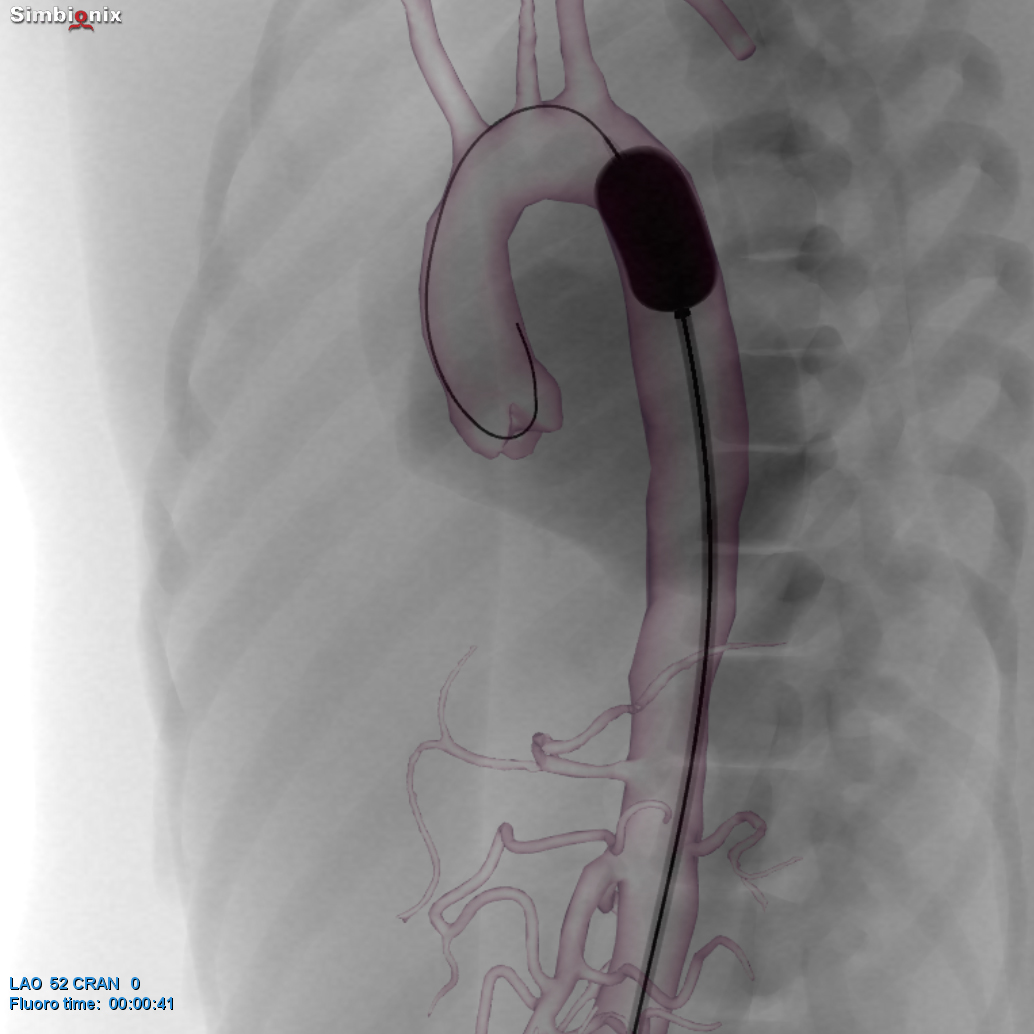

REBOA placement in zone III providing temporary aortic occlusion in the

REBOA placement in zone III providing temporary aortic occlusion in the How Does A Reboa Work resuscitative endovascular balloon occlusion of the aorta (reboa) has recently gained popularity as a minimally. resuscitative endovascular balloon occlusion of the aorta (reboa) is a minimally invasive technique using a balloon catheter to temporarily occlude the. The goal of reboa is to occlude blood flow to the major arterial vessel that is actively bleeding, and aortic insertion will. How Does A Reboa Work.